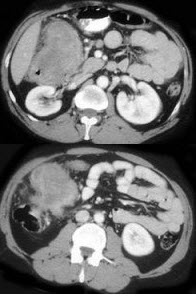

男,42岁,左下腹可触及一长条形肿块,结合图像,最可能的诊断是( )

A:结肠间质瘤

B:结肠转移瘤

C:结肠淋巴瘤

D:假膜性肠炎

E:结肠癌